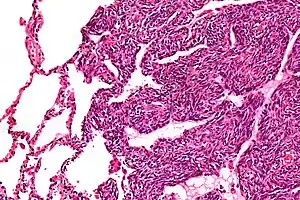

Micrograph of a monophasic synovial sarcoma. The histologic appearance is non-specific and overlaps with MPNST and fibrosarcoma. H&E stain.

Two cell types can be seen microscopically in synovial sarcoma. One fibrous type, known as a spindle or sarcomatous cell, is relatively small and uniform, and found in sheets. The other is epithelial in appearance. Classical synovial sarcoma has a biphasic appearance with both types present. Synovial sarcoma can also appear to be poorly differentiated or to be monophasic fibrous, consisting only of sheets of spindle cells. Some authorities[3] state that, extremely rarely, there can be a monophasic epithelial form which causes difficulty in differential diagnosis. Depending on the site, there is similarity to biphenotypic sinonasal sarcoma, although the genetic findings are distinctive.